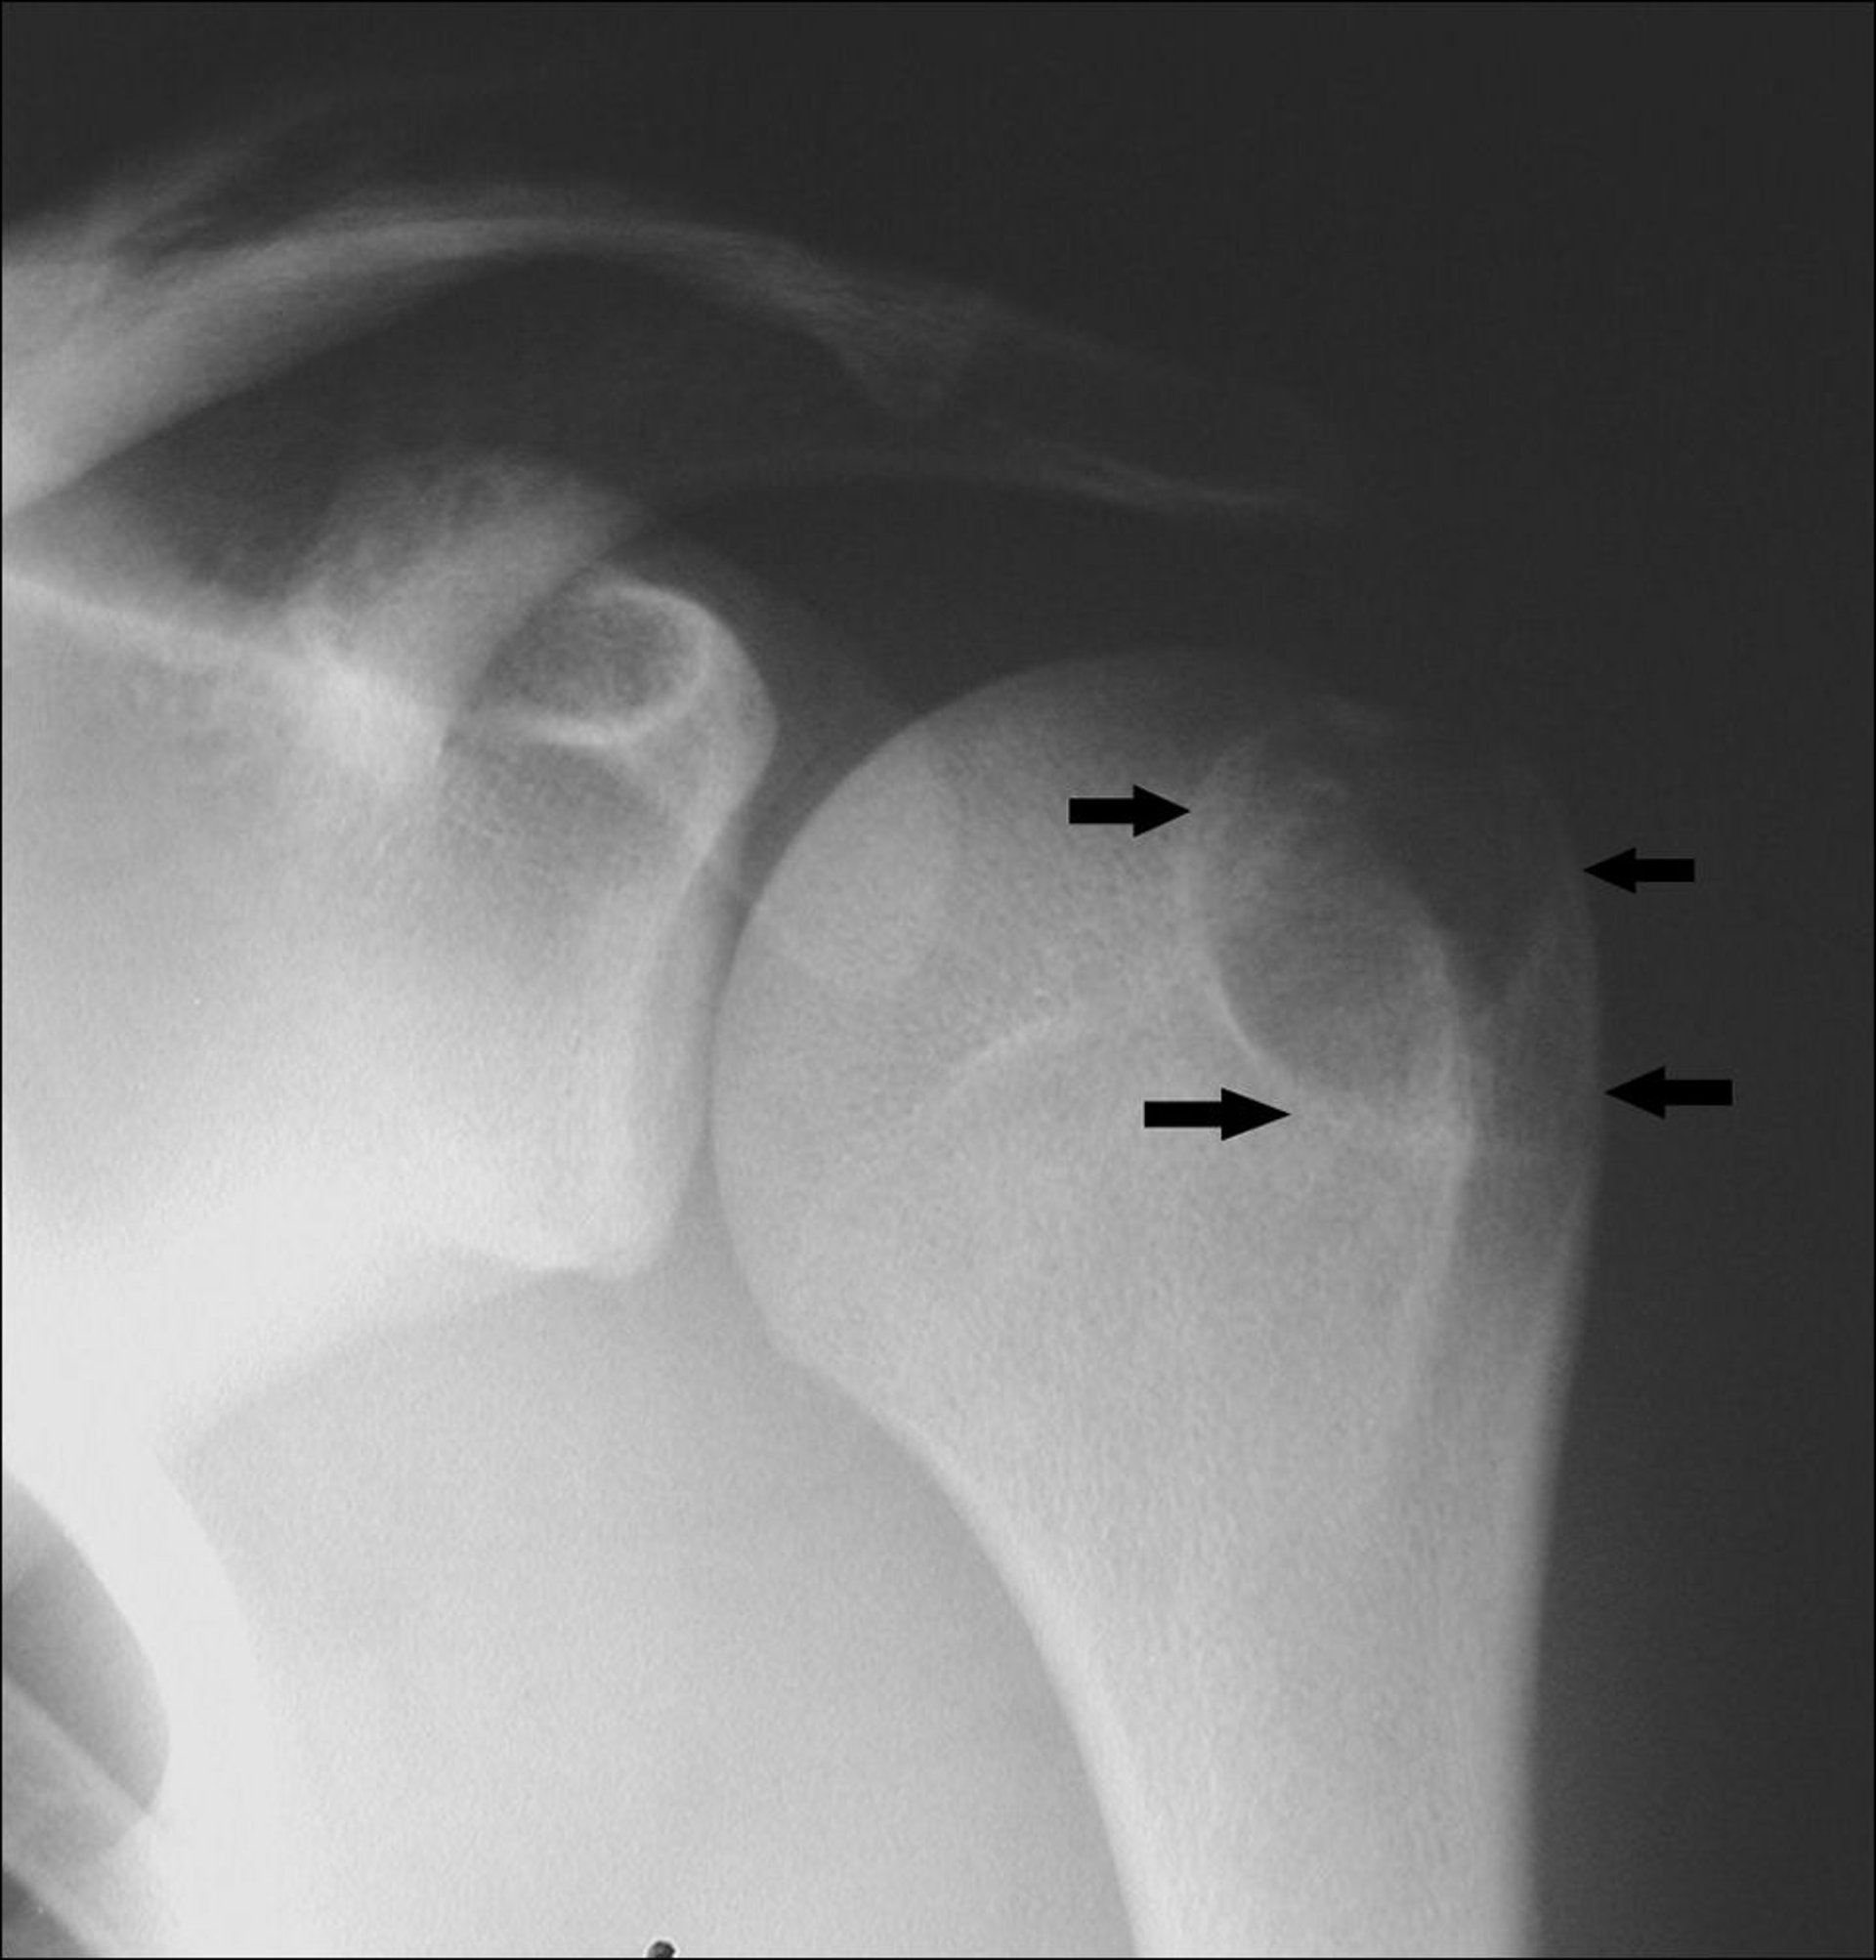

На данном рентгеновском снимке плеча показана хондробластома плечевой кости в области апофиза большого бугорка (стрелки).